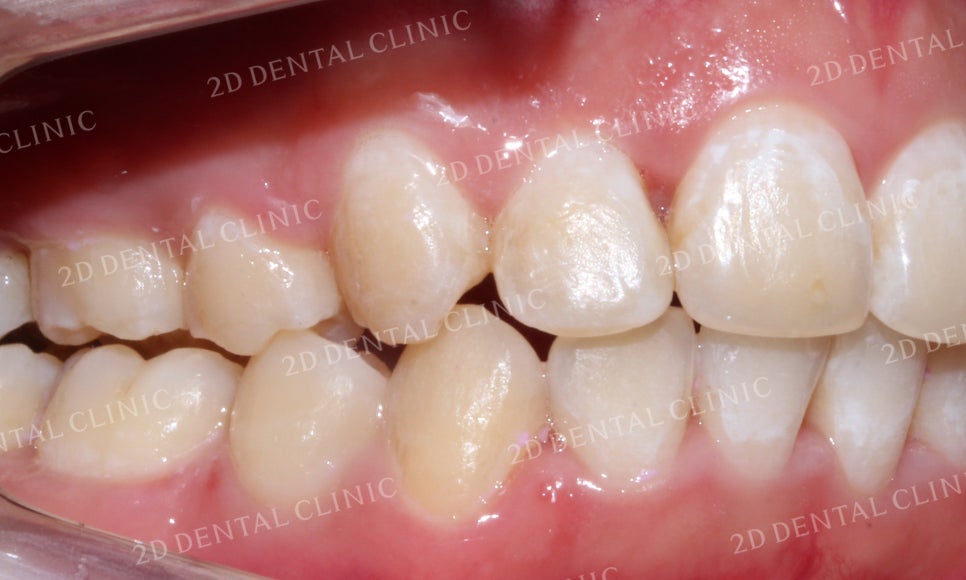

전치부의 측면 사진을 보시면

중절치가 돌출된 모습입니다.

전치부의 각도가 과도하게 전방으로

뻐드러져 있기 때문에 미약하게 성장한

하악이 상대적으로 더 작아 보이는 경향이 있습니다.